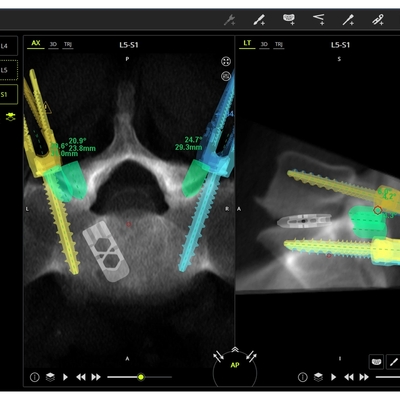

Click on an image below to view more info.